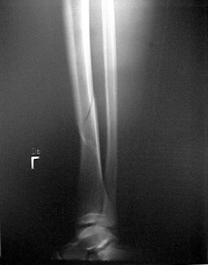

Fractura spirala de diafiza tibiala Fractura oblica de diafiza tibiala Fractura transversala de diafiza tibiala

Fracturi cominutive